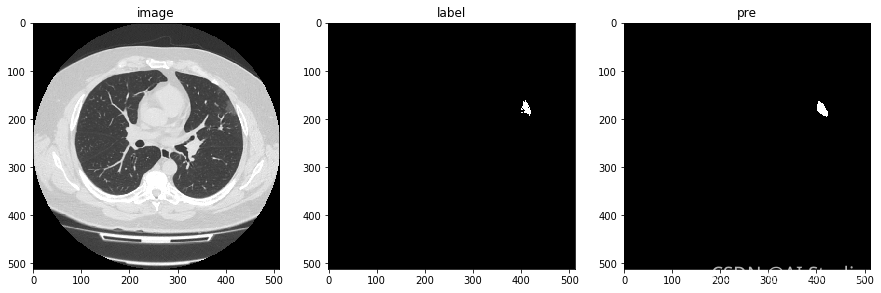

模型检测效果如下图:

对预测结果进行展示

可见模型对磨玻璃样病灶的细节分割并不是很好。但是这个项目的目地只是需要通过预测的mask结果在原图上画出病灶的轮廓,实现对病灶的检测和定位。告诉医疗那一层有磨玻璃样病灶,或者告诉医生那一层出现的磨玻璃样病灶面积是最大的。